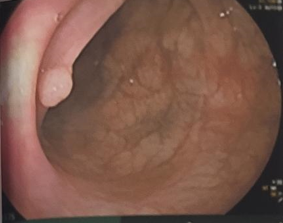

- Nội soi đại trực tràng:

Hình 2: Hình ảnh nội soi đại trực tràng: Đại tràng xuống và đại tràng sigma có 2 polyp kích thước  khoảng 0,3cm và 0,5cm